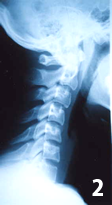

この症例(写真2)では、頚椎が前弯を失ってやや逆ぞりになっているのに加えて、前傾になって並んでいます。 この状態では頭からの重心線が首の前方にズレ(変位)しており、首には大きなストレスがかかった状態になっています。

この様に、頚椎が前傾すると、前傾の度合いが増すにつれて頚椎・首への負荷が増大することが判明しています。 頚椎が前傾すると、その重心線が1インチ(約2.54cm)前方に移動する毎に10ポンド(約453.6g)の負荷が頚部に加わります。

一般的に人間の頭は体重の1割程の重量がありますから、体重80Kgだと頭の重さは約8Kgです。 例えば、体重80Kgの男性で、頚椎が前傾して重心線が2インチ前方移動していれば、頚部に掛る負荷は約9Kgにもなるのです。